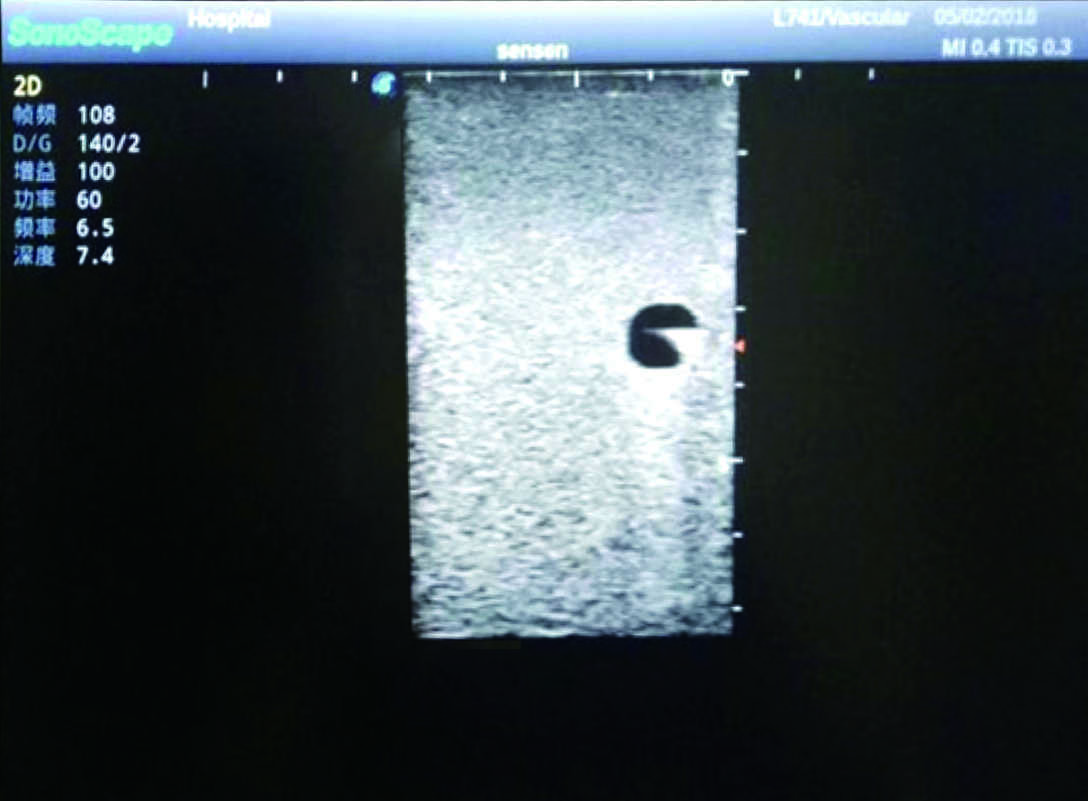

2)   It can be used by real ultrasound machines

3)   Clear and real images of the tissues and organs (basilic vein and superior vena cava)